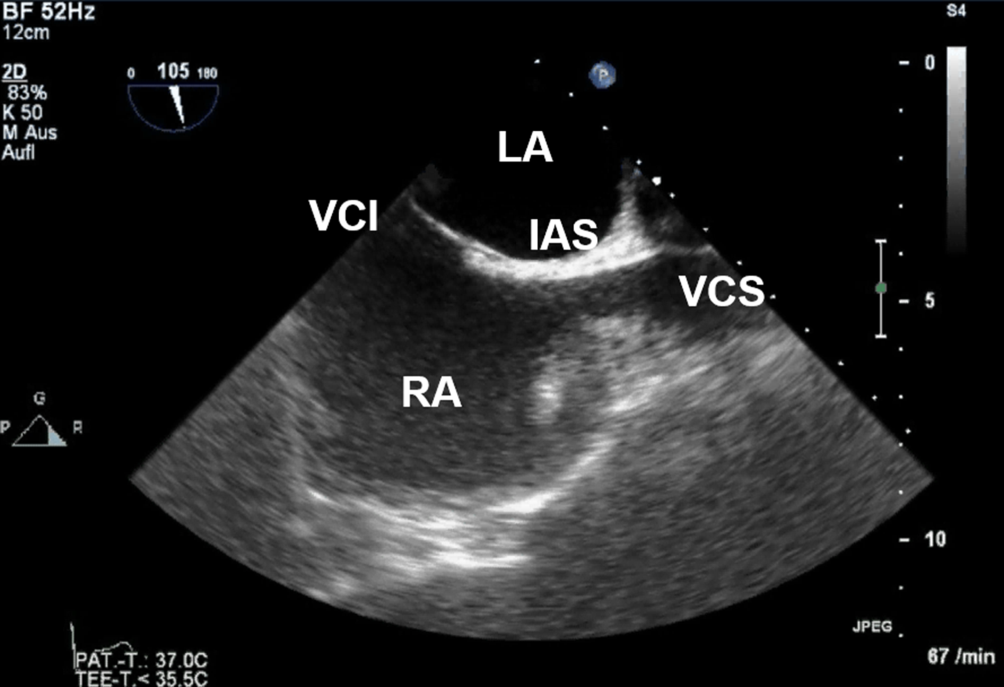

Anlotebene: bikavaler Blick

Sondenposition: mittösophageal (ggf. leichte mechanische Längsrotation der Sonde nach rechts im Uhrzeigersinn)

Rotationswinkel: 100°